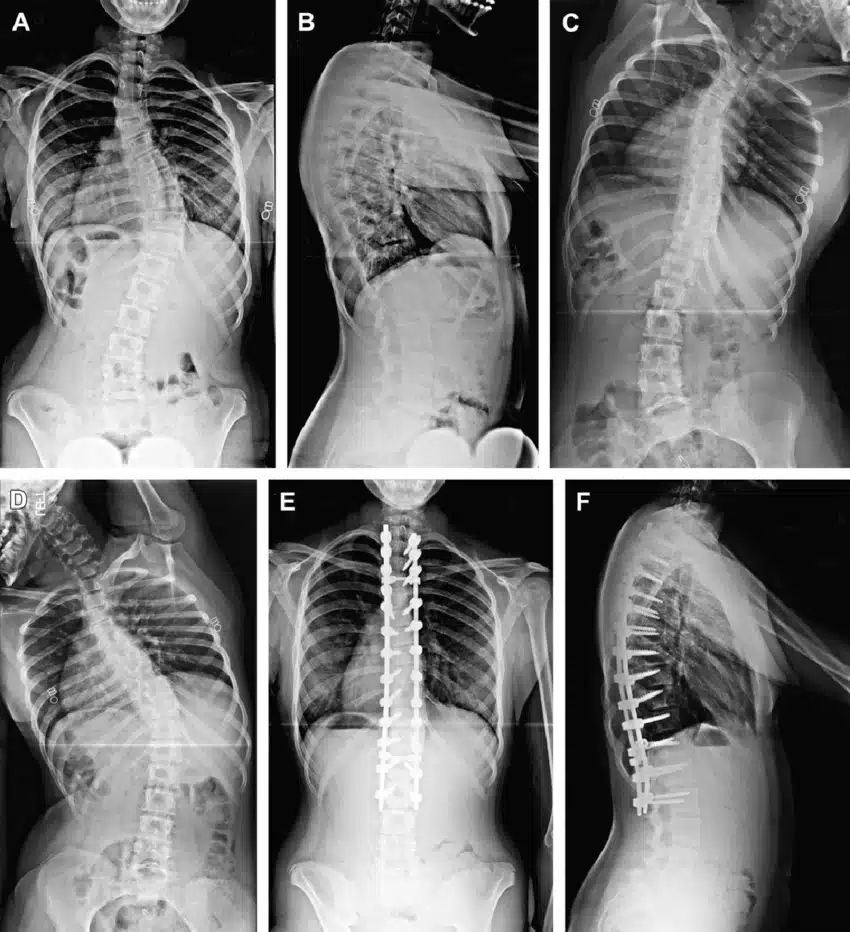

To identify spinal stenosis, your physician may request you about signs and symptoms and then performs a physical examination. He may perform several imaging tests to determine the cause of your signs and symptoms. Imaging tests may include X-Ray or MRI. Your X-ray or MRI can show bone changes, such as spur bones, which may narrow the space in the spinal canal and the doctor prescribes you spinal canal stenosis surgery.

Treatment of spinal stenosis depends on the location of the stenosis and the severity of the symptoms. Talk to your doctor about the right treatment for your problem. If your symptoms are mild or you are experiencing nothing, your doctor may monitor your condition with regular appointments. He may offer some self-care advice that you can do at home. If they do not help, they may prescribe medication or physiotherapy. If other treatments have not helped, spinal canal stenosis surgery may be an option. Surgery can be suggested if other sort of treatments do not help the patient. Surgical goals include relieving spinal cord pressure or nerve roots by making additional space in the spinal canal. Instances of surgical procedures to treat spinal stenosis include:

There are different treatment options for canal stenosis. For example, stenosis in the lower back can be treated by physical therapies and medications. In the case of no improvements, surgical treatment is recommended. During the surgery, the bony element will be removed so that the pressure over the nerve will decrease. Occasionally, surgery will be performed by the use of rods and screws.